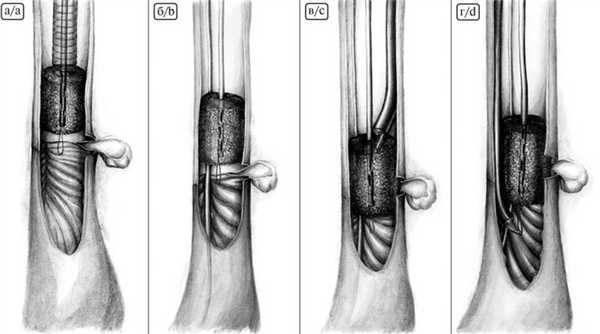

При создании эндоскопической ВАС использовали губчатую систему с открытыми сообщающимися ячейками для лечения осложненных и хронических раневых инфекций размером 10×7,5 см и толщиной 3,3 см (рис. 4, А). Рис. 4. Пошаговое моделирование вакуумно-аспирационной системы. А — губчатая система с открытыми сообщающимися ячейками размером 10×7,5 см и толщиной 3,3 см; Б — моделирование губки в форме цилиндра; В — назогастральный зонд, на котором моделировали систему; Г — фиксация губки на дистальном конце зонда; Д — фиксация губки проксимально; Е — окончательный вид системы. Такие размеры губки позволяли сделать 2 ВАС с использованием стандартного зонда для аспирации содержимого желудка.

Губку моделировали в форме цилиндра диаметром, не превышающим диаметр пищевода, и длиной, перекрывающей минимум на 2 см дистальную и проксимальную границы зоны несостоятельности (см. рис. 4, Б). В губку проводили «желудочный» зонд и фиксировали его 2 швами — на дистальном конце зонда и проксимально (см. рис. 4, В, Д). Здесь же из лигатур формировали 2 петли для позиционирования губки. На рис. 4. Е представлен окончательный вид ВАС.

Для установки ВАС применяли собственную разработанную методику. С этой целью использовали overtube с внутренним полым стилетом, через который можно провести эндоскоп (рис. 5, А—В). Рис. 5. Overtube с внутренним полым стилетом — А и Б; В — внешний вид эндоскопа с надетым на него overtube.

Это приспособление (overtube) под эндоскопическим контролем устанавливали в просвет пищевода до зоны несостоятельности анастомоза. В дальнейшем по нему с помощью внутреннего стилета проводили ВАС (рис. 6, А; Рис. 6. Эндоскопическая картина установки и позиционирования вакуумно-аспирационной системы. А — система проведена в просвет пищевода; Б — вдоль системы проведен зонд для питания; В, Г — эндоскопически ассистированное позиционирование системы. рис. 7, А). Рис. 7. Схема установки и позиционирования вакуумно-аспирационной системы. А — система проведена через overtube в просвет пищевода к зоне анастомоза; Б — overtube извлечен, вдоль системы проведен зонд для питания на противоположной стороне от зоны несостоятельности; В, Г — эндоскопически ассистированное позиционирование системы.

После этого overtube извлекали из просвета пищевода и следующим этапом мимо ВАС через инструментальный канал в просвет тонкой кишки устанавливали зонд для питания, позиционируемый вдоль ВАС с противоположной стороны от зоны несостоятельности (см. рис. 6, Б; 7, Б). Окончательным этапом выполняли эндоскопически ассистированное позиционирование ВАС в область несостоятельности анастомоза таким образом, чтобы зона дефекта располагалась непосредственно посередине губки (рис. 8). Рис. 8. Эндоскопическая картина соотношения вакуумно-аспирационной системы (желтые стрелки) и зоны несостоятельности анастомоза (красные стрелки).

Это достигалось путем захватывания ранее сформированных лигатурных петель на проксимальном и дистальном концах губки с помощью эндоскопической цапки, проведенной через инструментальный канал (см. рис. 6, В, Г; 7, В, Г).

После установки и позиционирования губки проксимальный конец ВАС и несущий ее зонд выводили через нос и подключали к активной аспирации с разрежением 100—110 мм рт.ст.